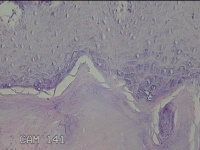

左拇指结节

性别

男

年龄

42岁

临床诊断

皮下结节

一般病史

发现左拇指结节8年余。

标本名称

大体所见

灰白粉红色组织1.3x0.8x0.3cm一块,表面带梭形皮肤1.3x1.1cm,皮下见结节0.8x0.5cm一个,切开结节呈实性,切面灰白粉红色,质中。

良性病变。